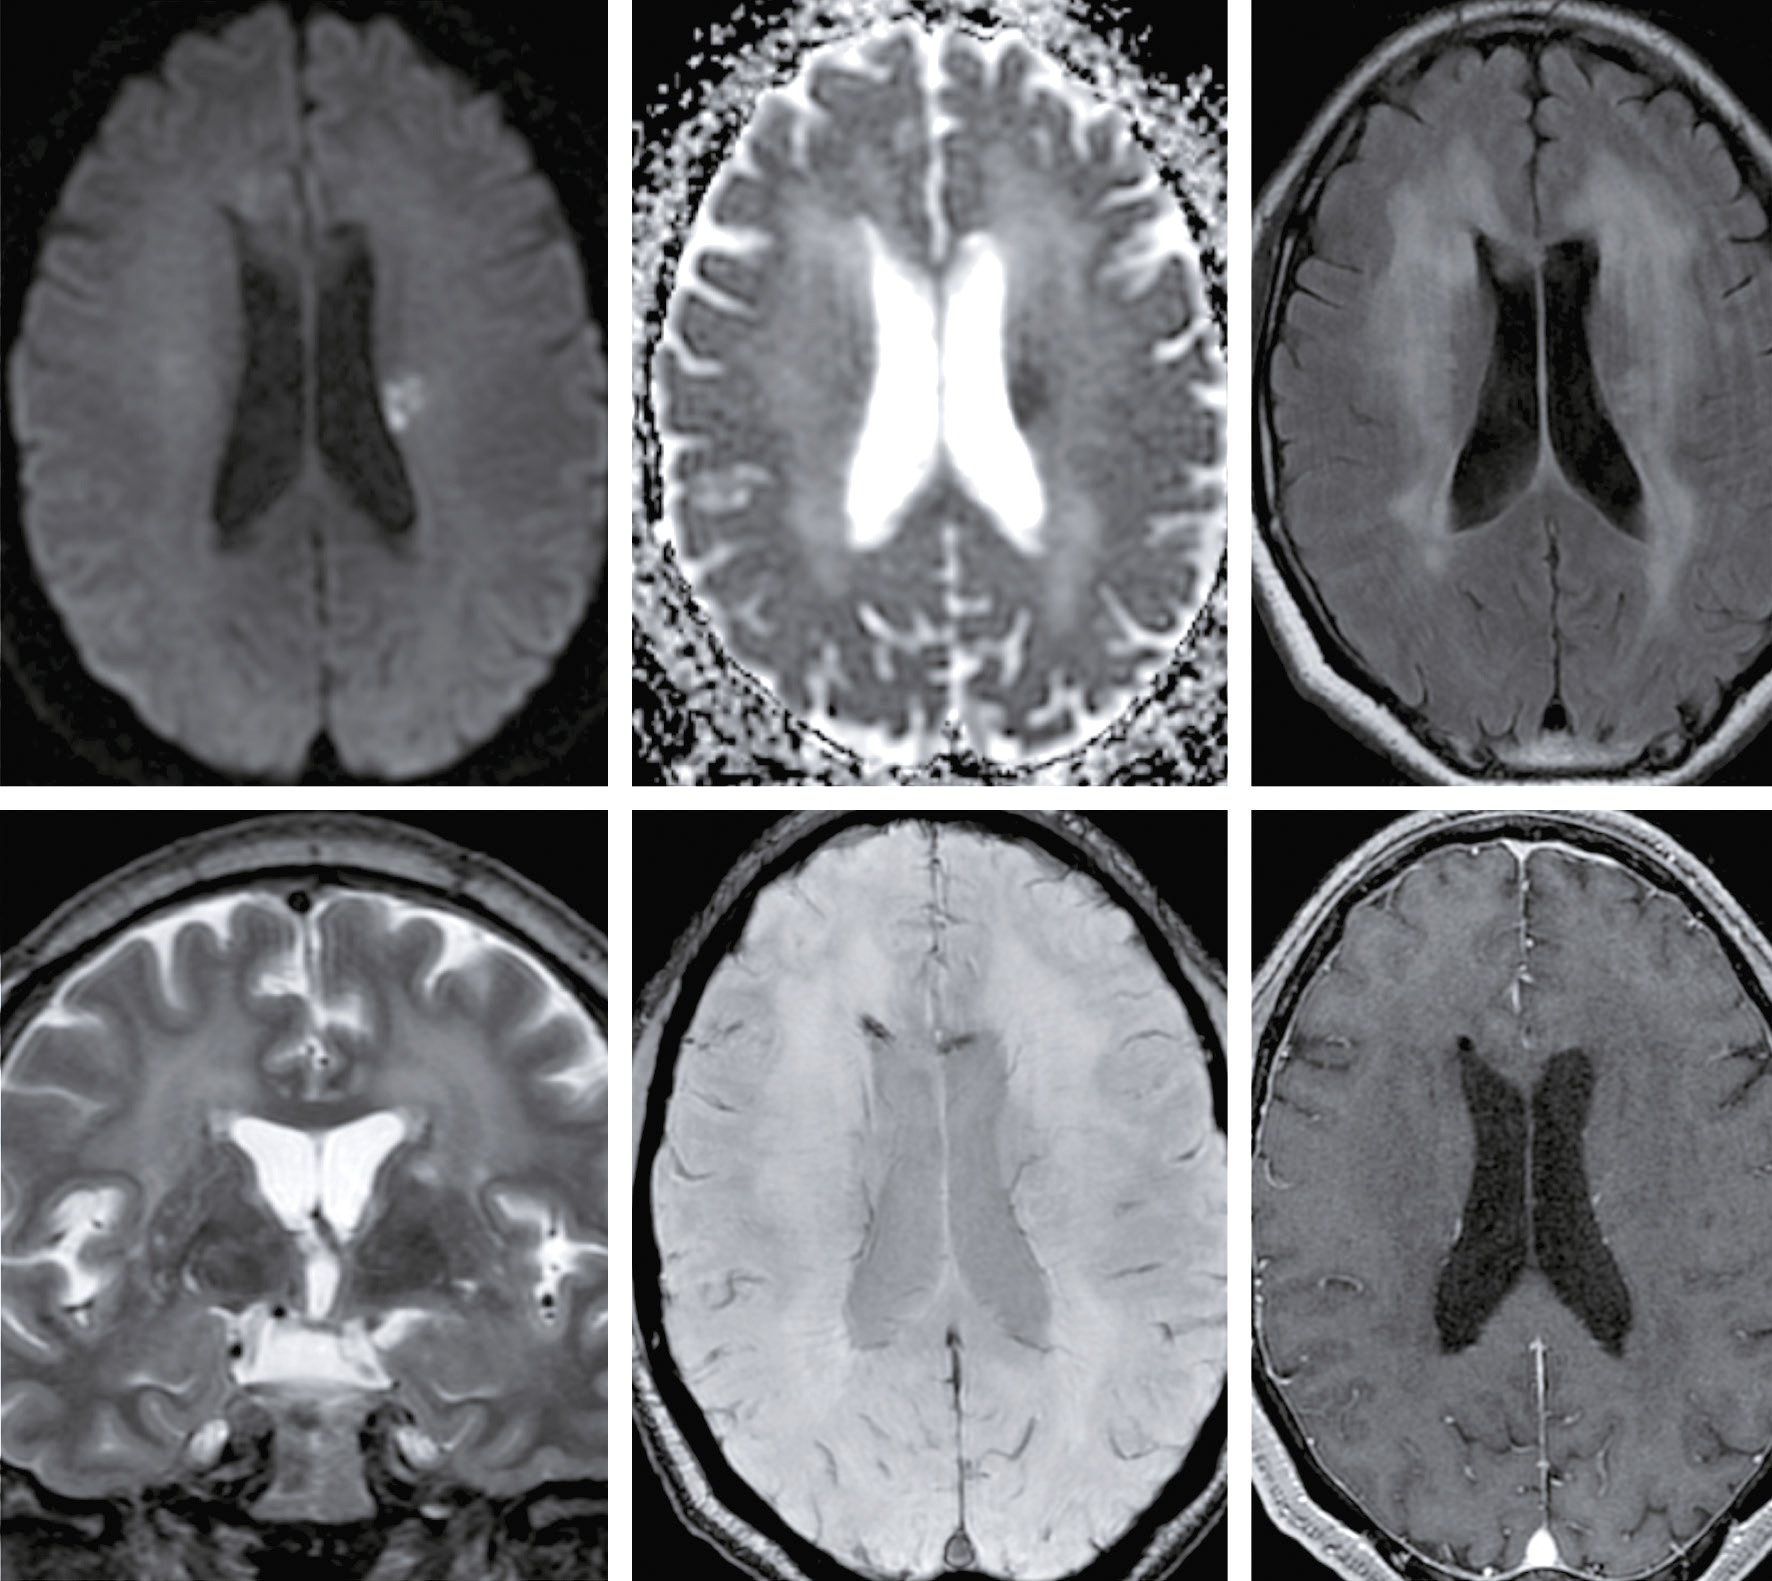

Vous débutez un traitement par benzodiazépine, vitaminothérapie B1, B6, PP, réhydratation par sérum salé et immunoglobulines polyvalentes intraveineuses associées à une héparine de bas poids moléculaire à dose isocoagulante. Le lendemain matin, le patient s’est aggravé d’un point de vue clinique. Il n’a plus d’hallucination visuelle mais il présente maintenant une tétraparésie évaluée à 3/5 avec ataxie des quatre membres, une dysarthrie, des troubles de la déglutition, et une ophtalmoplégie bilatérale. Un bilan biologique a été prélevé avant votre arrivée : numération formule sanguine : Hb : 13,8 g/dL, leucocytes : 8 600/ mm3, plaquettes : 332 000/mm3, ionogramme sanguin : Na+ : 142 mmol/L, K+ : 4,2 mmol/L, clairance de la créatininémie : 92 mL/min, glycémie : 5,8 mmol/L, transaminases, phosphatases alcalines, bilirubines et γ-GT normales, CRP : 3 mg/L.

Une IRM cérébrale a été également réalisée (fig. 31.4). Quelle est la séquence présentée ?

L'image montre une IRM (Imagerie par Résonance Magnétique) du cerveau humain en coupe axiale, c'est-à-dire une vue transversale du cerveau prise horizontalement. Cette image est particulièrement intéressante car elle permet de visualiser les structures internes du cerveau avec une grande précision. On peut observer les globes oculaires en haut de l'image, qui apparaissent comme deux cercles blancs. Les différentes zones du cerveau sont visibles, avec des variations de teintes qui indiquent les différentes densités des tissus cérébraux. La région centrale lumineuse correspond au tronc cérébral, une structure cruciale pour de nombreuses fonctions vitales. Les zones plus sombres autour du tronc cérébral représentent les hémisphères cérébraux. Cette image est utilisée pour diagnostiquer et évaluer diverses conditions neurologiques, telles que les tumeurs, les accidents vasculaires cérébraux, les infections, et les anomalies structurelles. L'IRM est une technique non invasive qui utilise des champs magnétiques et des ondes radio pour produire des images détaillées des organes et des tissus internes.

- A T1

- B écho de gradient

- C T2

- D T2/FLAIR

- E diffusion